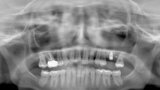

Fig. 14: Dental panoramic tomogram of initial situation.